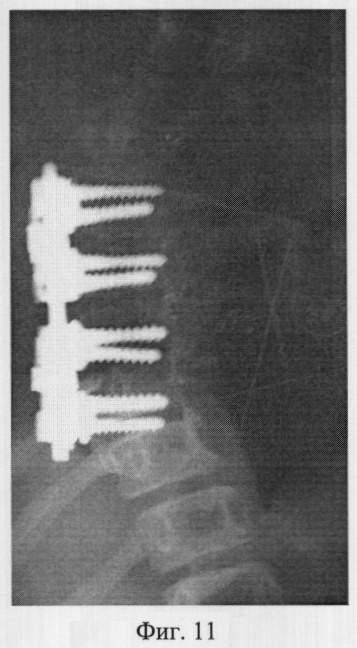

Фиг.11 – рентгенограмма в прямой проекции позвоночника больной X. после операции вентральной коррекции центрального угла деформации и фиксации из переднего доступа;

Пример 3. Больная X., 11 лет, 08.07.05 поступила в отдел новых технологий в вертебрологии и нейрохирургии СарНИИТО по поводу диспластического прогрессирующего нестабильного правостороннего грудопоясничного сколиоза III степени.

В СарНИИТО ей были выполнена рентгенография в стандартных проекциях: фасная (фиг.9) и боковая (фиг.10) рентгенограммы.

По фасной рентгенограмме определены следующие показатели позвоночника:

– угол сколиотической деформации по Кобб: стоя – 50°, лежа – 48°;

– индекс стабильности по Казьмину – 0,82;

– определена протяженность дуги в 7 позвонков (от Th3 до Тh11),

– определена вершина деформации – Th6.

По рентгенограммам проведена оценка зрелости позвоночника: тест Риссера составил R-1, кольцевые апофизы тел позвонков четко определены у тел Th4-Th9, Тh10 по дуге искривления, что свидетельствует о высокой потенции роста больной и прогрессировании деформации.

Поэтому выполнение оперативного вмешательства из заднего доступа в полном объеме невозможно. Выполнение заднего спондилодеза при протяженности деформации в 7 позвонков (Th3-Th11) в сочетании с высоким потенциалом роста и открытыми пластинками роста позвонков может привести в последующем к формированию тяжелой деформации позвоночника по типу синдром «коленчатого вала».

Заключение: при протяженности сколиотической дуги в 7 позвонков с вершиной деформации в пределах одного грудного отдела позволяет провести вентральную коррекцию центрального угла деформации и фиксацию металлоконструкцией из переднего доступа.

На основании расчета морфометрических параметров позвонков выбраны 8 винтов длинной по – 25 мм, диаметром по – 5 мм.

12.07.05 больной выполнена вентральная коррекция и фиксация сколиотической деформации из переднего доступа металоконструкцией «Antares» фирмы «Medronic».

В послеоперационном периоде выполнены контрольные рентгенограммы: в фасной (фиг.11) и боковой (фиг.12) проекциях. Угол остаточной деформации по Кобб 20°, степень коррекции 30°, что соответствует 60% от первоначальной деформации.